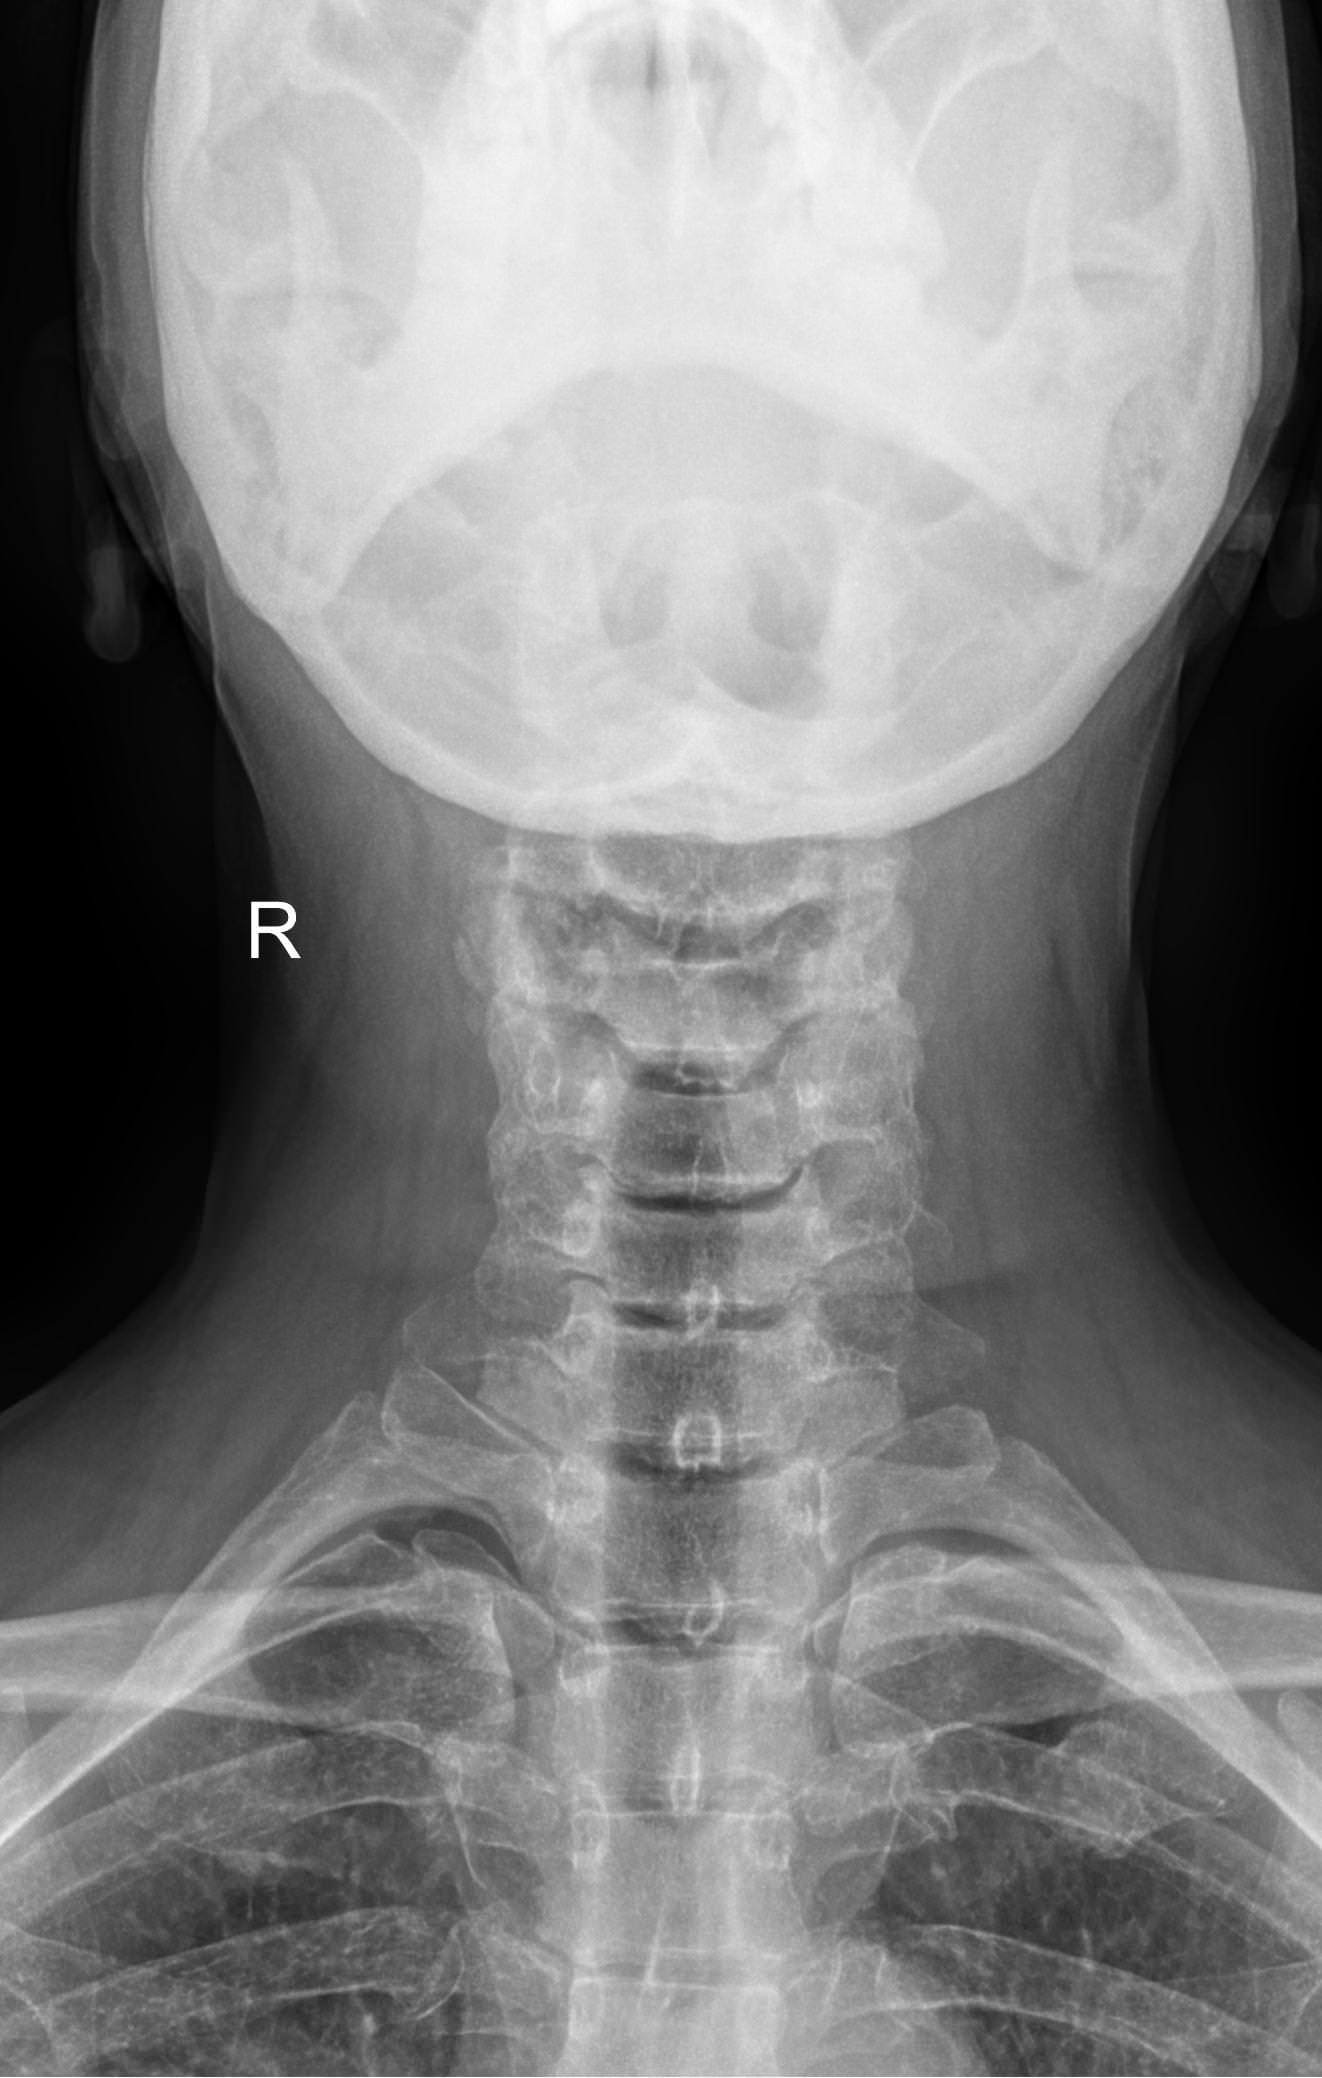

Функциональные исследования помогают выявить гипермобильность шейных позвонков или функциональный блок. Часто пробы позволяют определить начало остеохондроза, признаки которого на снимках в прямой и боковой проекции еще не заметны.

• Сохранение или сглаживание естественного лордоза в нейтральном положении, то есть на первом снимке;

• Смещение вперед или назад каждого позвонка по отношению к нижележащим при сгибании и разгибании;

• Деформацию передней стенки позвоночного канала из-за смещения позвонков;

• Сужения, расширения или отсутствие изменений межпозвоночных пространств;

• Изменения формы тел позвонков, наличие остеофитов;

• Аномалии развития.

В качестве подготовки необходимо снять все металлические украшения с шеи и головы, расстегнуть пуговицы и надеть защитную накидку. Диагностика выполняется в положении стоя или сидя, всего делается 3 снимка:

• В боковой проекции ― строго боком к детекторной пластине;

• В условиях максимального разгибания головы назад;

• В положении максимального наклона головы вперед.